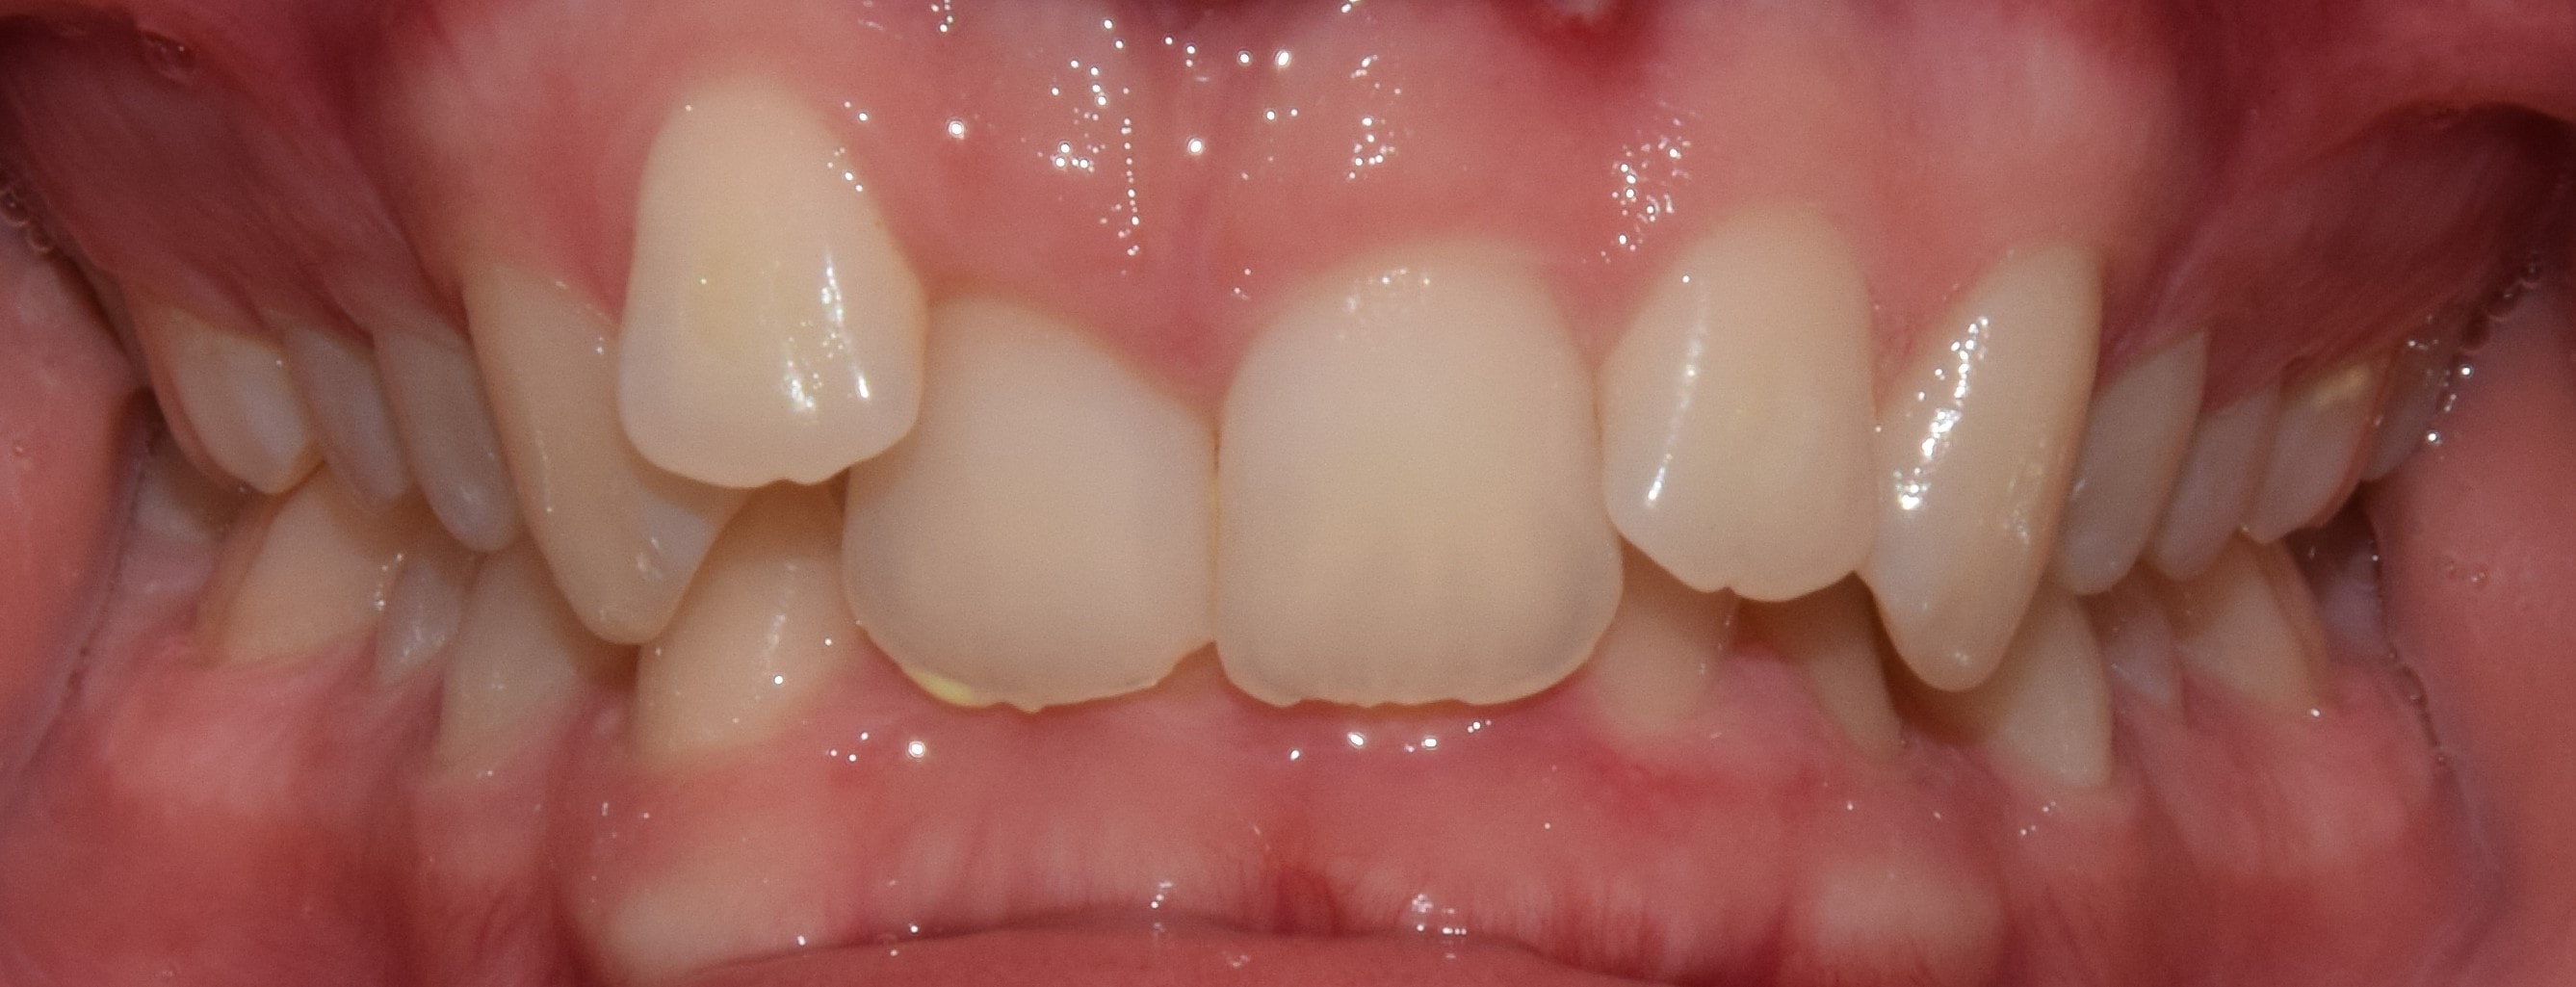

Diasthema medianum

Gyakori fogszabályozási probléma a két felső nagymetsző között jelentkező rés. Ellátását számos faktor befolyásolja. A vegyesfogazatban gyakori, legtöbbször normális jelenség, ami később spontán záródhat, ezért túlságosan korai ellátását semmi sem indokolja. Diasthemat eredményezhet például kifejezett ajakfék, számfeletti fog, kismetsző csírahiány.